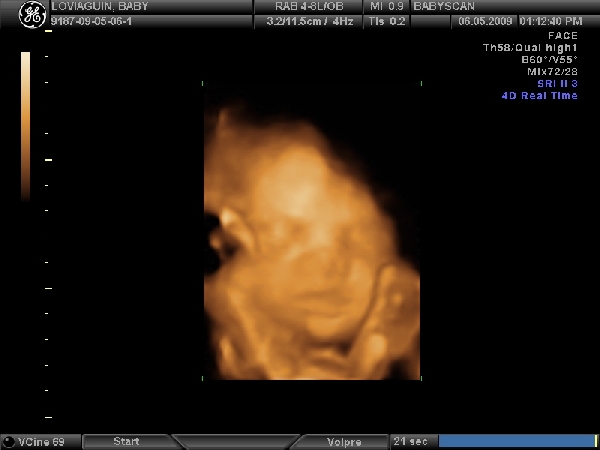

Nemsokara keszulok 3d-re!!!!Delutan 1/2 2-re kell menni,remelem most ezek jobban odafigyelnek majd,mert az elozo,ahol a 21.heten voltunk,na az katasztrofa volt....unott csaj,folyamatos basztatas hogy meg kicsi,ennek igy semmi ertelme... :shock: :evil:

Ezeknel mar voltam a 12.hetin,es a genetikai uh-n,es rendesek,turelmesek,kedvesek voltak.

Na es akkor...!

Megvolt az uh,edes kis lanykat novesztgetek pocakomban.Kisse szegyenlosnek mutatkozott,az istenert sem akarta a kezet elvenni az arca elol,sot kesobb a masik kezevel is fogta a fejet...es egy lab is bejatszott a kepbe :lol: :lol: :lol:

Kaptunk vagy 40db.kepet 8) lattuk minden porcikajat!Vegre a ket szemunkel a nuncijat is :lol: !Turelmes,rendes,kedves dokineni csinalta....elegedett vagyok apaval egyutt.Sikerult megint elpityerednem,persze a buszke apuka is csak amuldozott a lanyan!!!

Mereteink:

BDP(fejatmero):7,56cm

HC(fejkorfogat):28,0cm

AC(haskorfog.):26,78cm

FL(combcsont):5,96cm

HL(felkarcsont):5,49cm

becsult suly:1654gr.

Szoval teljesen rendben vagyunk,remenykedtem hogy nem produkalunk orias mereteket,mindenki riogat a hasmeretem alapjan....jo lenne ha nem lenne egy benga orias bebi :lol: :lol: 8)

Meretek alapjan julius 8 koruli a szuletesi ido.De nem modositok,jo ez igy ez a tol-ig idopont...